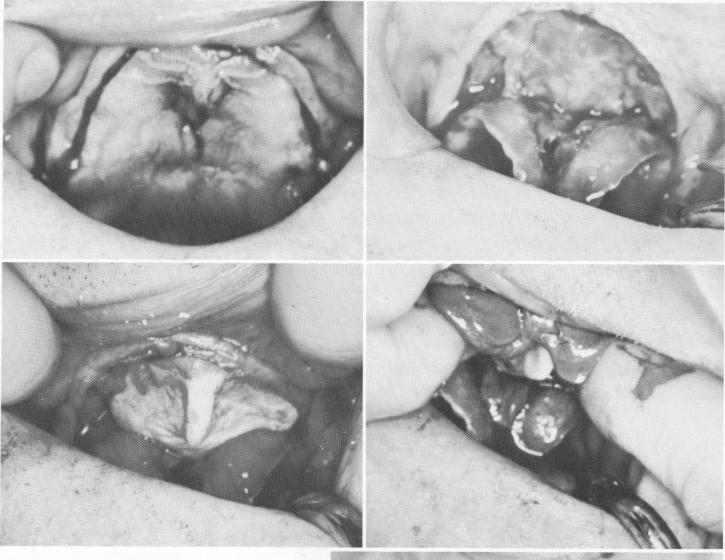

Fig. 12-112. A, The subperiosteal toroplant contains three parallel posts and two holes for fixative screws. B, The casting was commercially radio-graphed for porosities.